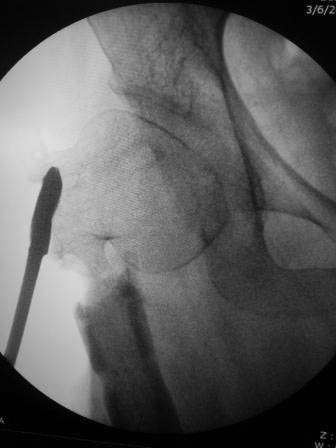

Уважаемые коллеги. Больная оперирована 06.03.15г клинок был сломан,

и пока его с трудом  удалили  от неполноценного вертела почти ничего не

осталось,сломанный шуруп тоже удален, шейка совсем короткая, , ШДУ

около 95гр, из-за сильного остеопороза при сверление в положении чуть

вальгуса наружная стенка крошится , и еще что интересно при первой

операции головка бедра оказалось фиксирован в положении ретроверсии

примерно 10-15 гр.. и с трудом удалось выпрямить головку и шейку до 0

гр. , укорочение было чуть больше 1см , п/о -2см, пока фиксация гипсовый

сапожок с деротатором. Дальше как быть? Может временно фиксировать